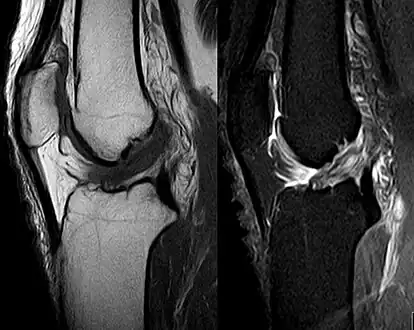

Medical imaging

Though clinical examination in experienced hands can be accurate, the diagnosis is usually confirmed by magnetic resonance imaging, which provides images of the soft tissues like ligaments and cartilage around the knee.[1] It may also permit visualization of other structures which may have been coincidentally involved, such as the menisci or collateral ligaments.[29] An x-ray may be performed in addition to evaluate whether one of the bones in the knee joint was broken during the injury.[9]

MRI is perhaps the most used technique for diagnosing the state of the ACL, but it is not always the most reliable technique as the ACL can be obscured by blood that fills the joint after an injury.[30]